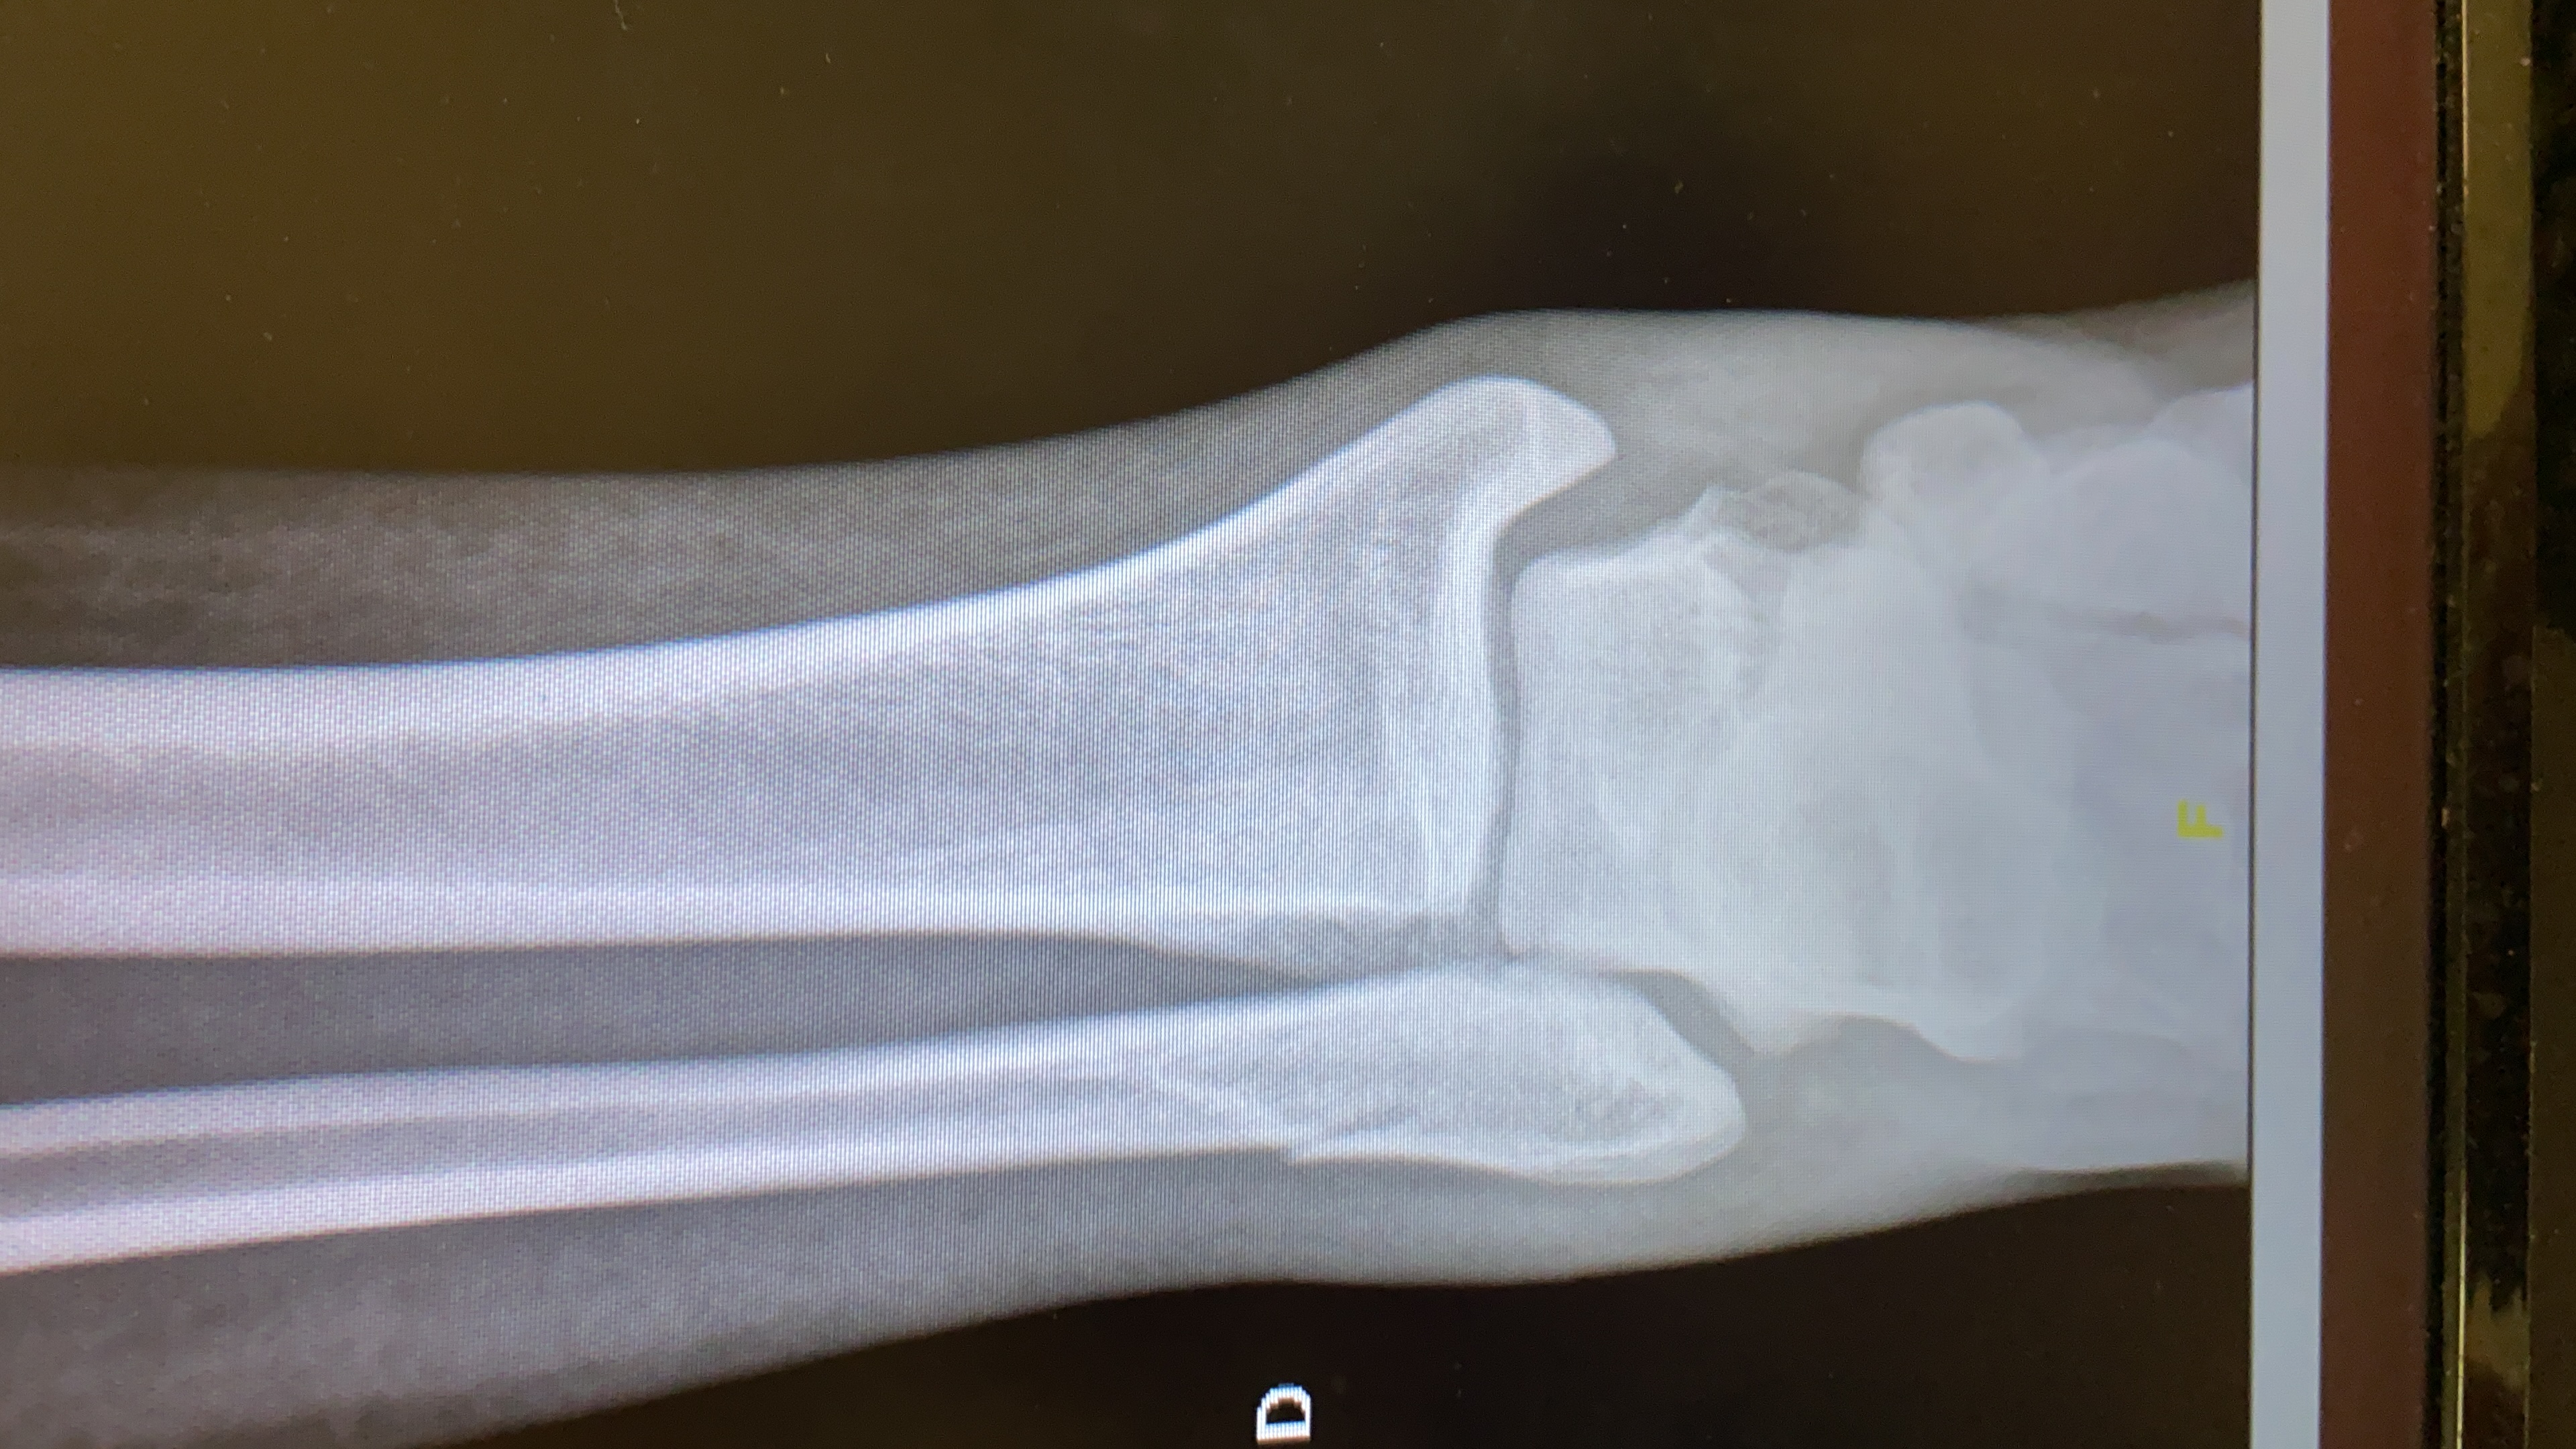

Fraturas do tornozelo

As fraturas do tornozelo podem ser resultantes de uma ampla variedade de trauma. Traumas de baixa energia tais como entorses ou de alta energia como acidentes de trânsito. São lesões comuns na prática ortopédica porém podem causar sequelas irreversíveis. Podem ser tratadas de modo conservador com imobilização e analgesia ou cirurgia dependendo do grau da lesão. Na dúvida procure seu ortopedista de confiança #drluizperesfilho #fratura de tornozelo